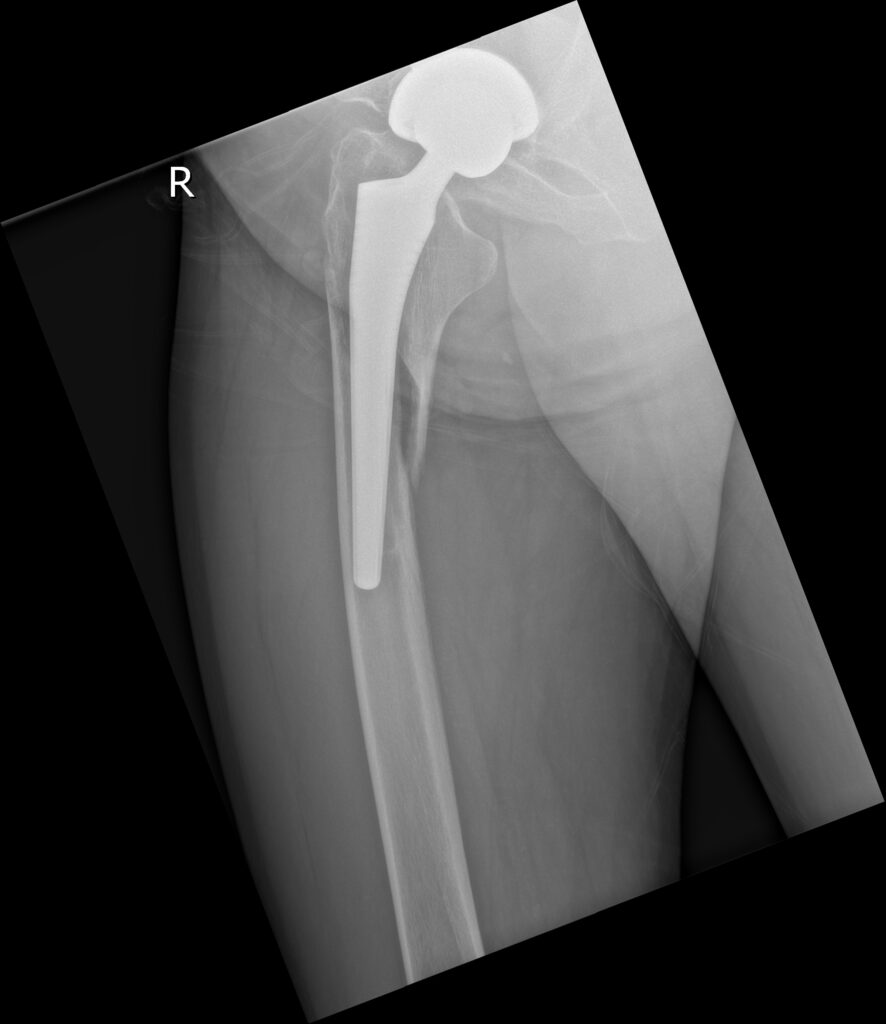

全髋术后股骨侧假体周围骨折切开复位内固定股骨柄翻修术(Open reduction, internal fixation and femoral stem revision for periprosthetic fractures on the femoral side after total hip surgery)